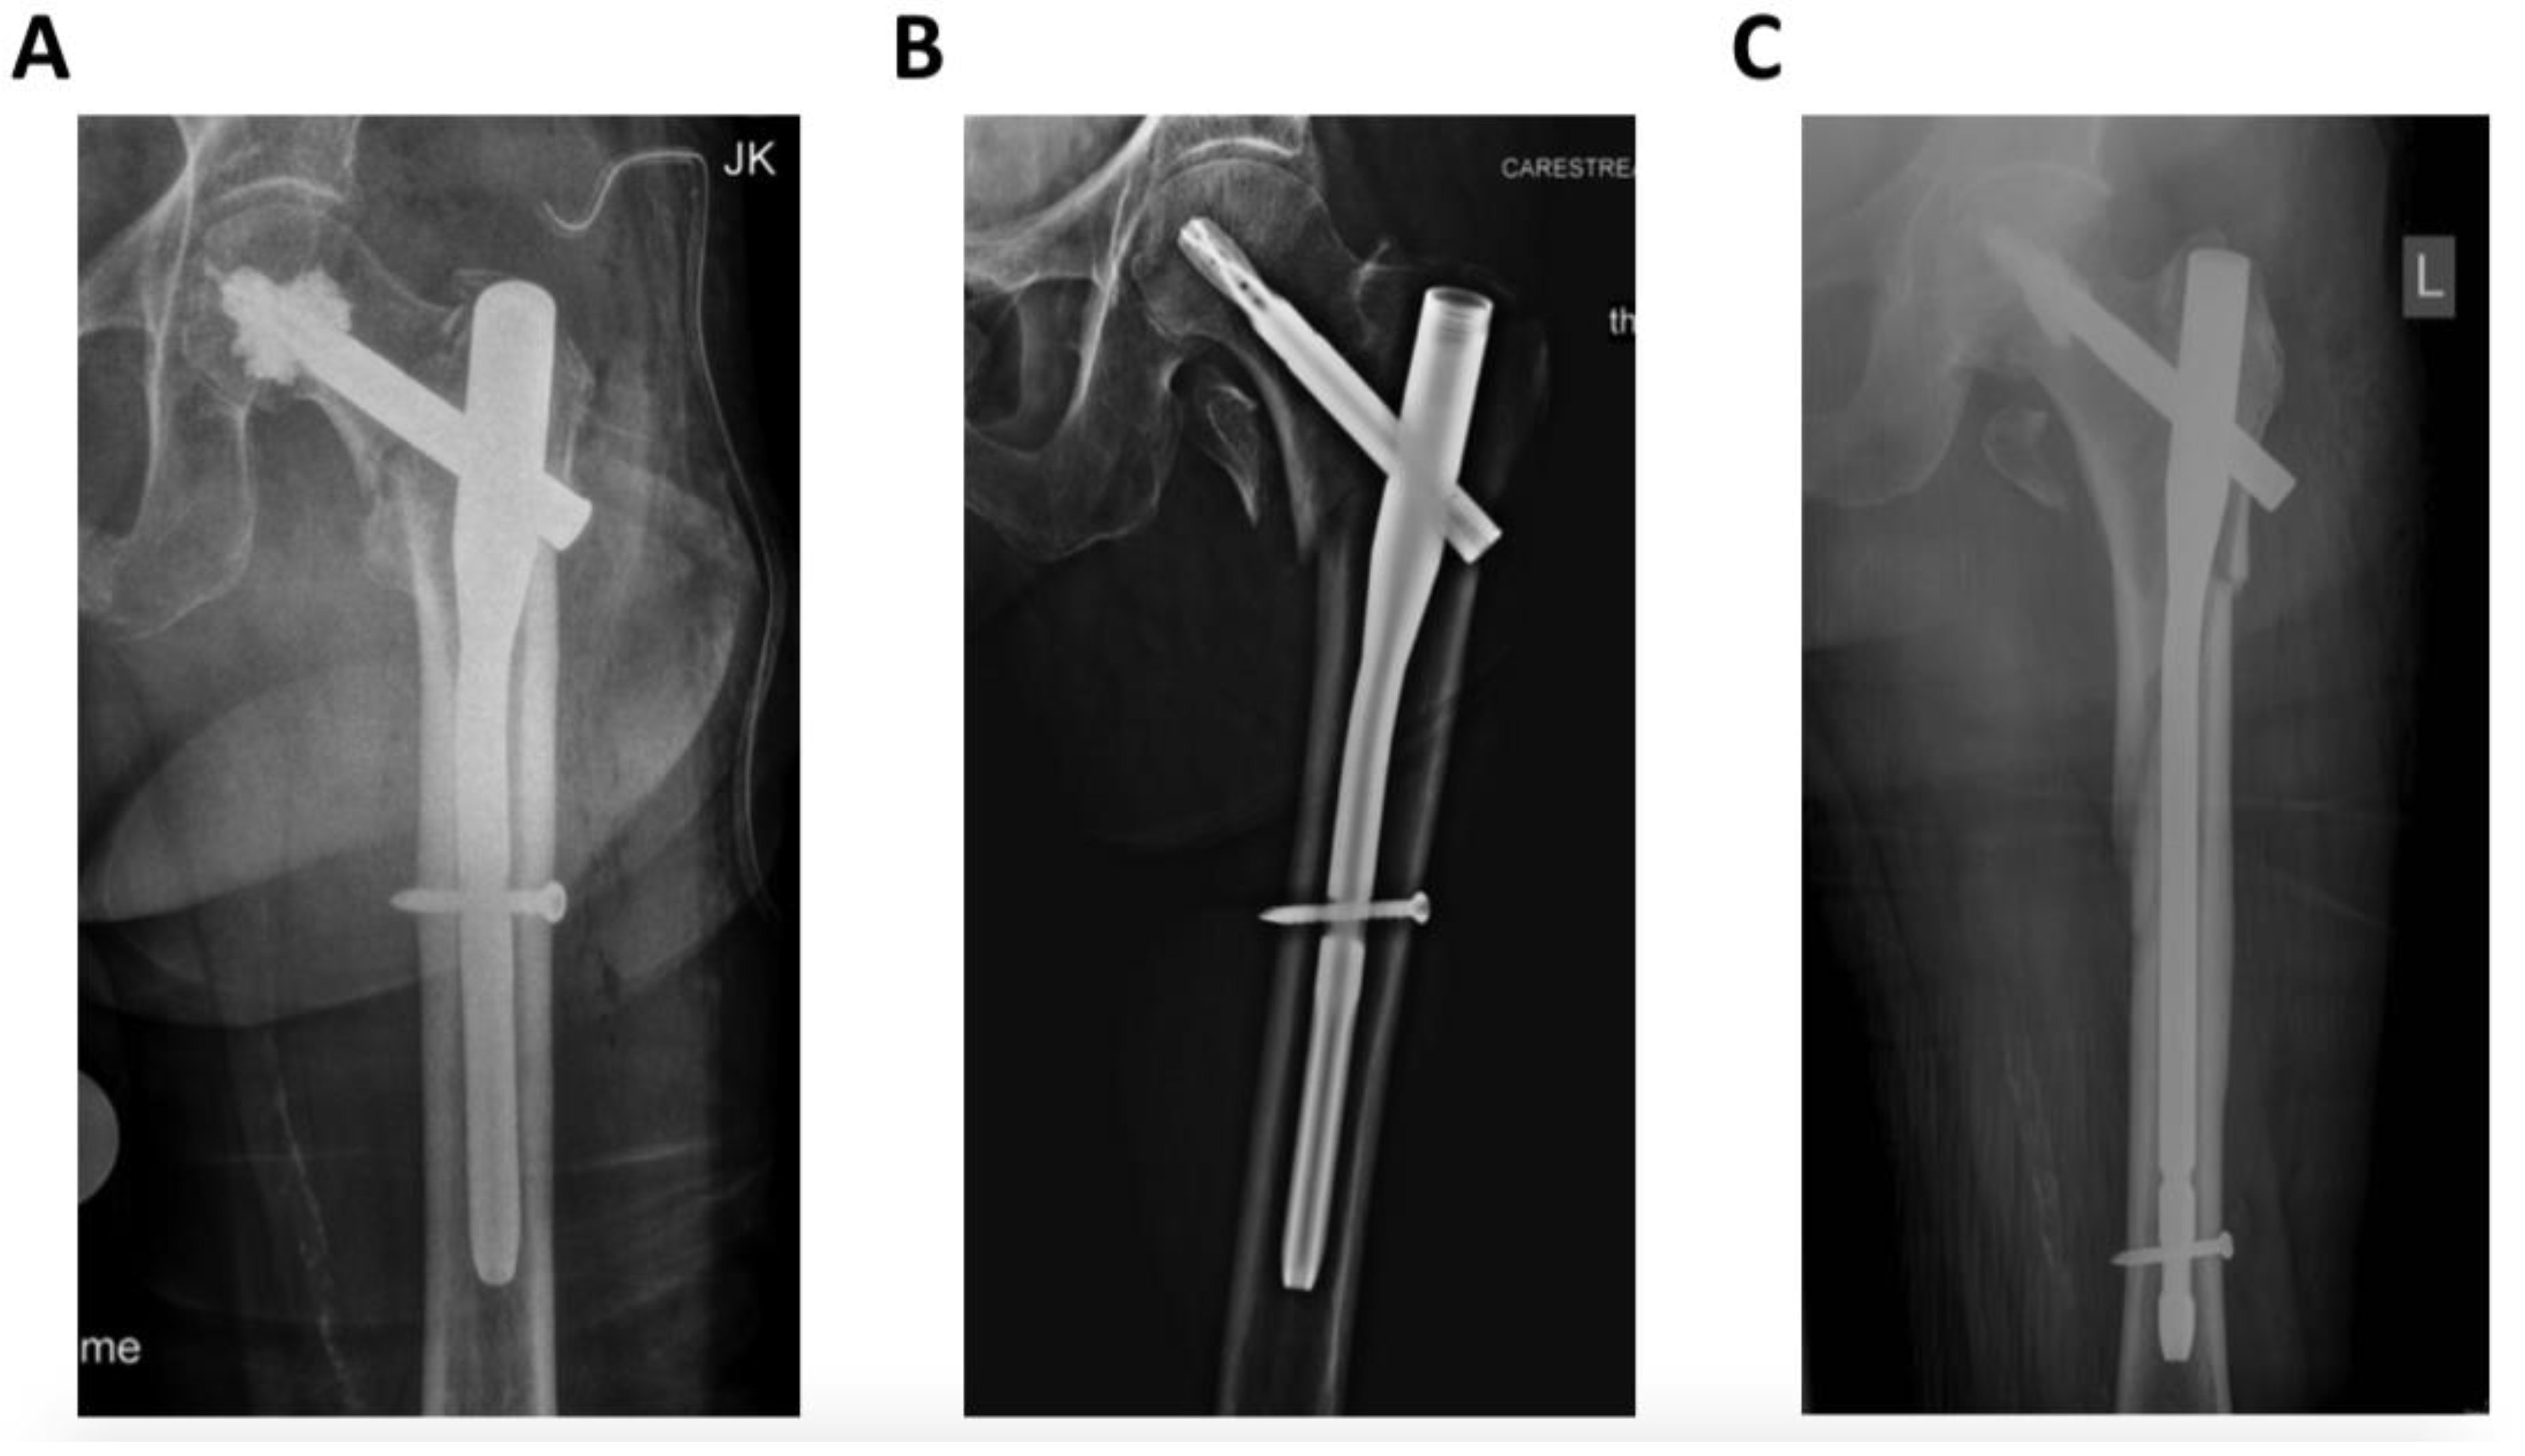

Due to the different treatment regimes, frequency of open reduction significantly increased from stable 31A1 (0%) towards unstable 31A2 (32%) and 31A3 (71%) fractures (A1/A2 p < 0.001; A1/A3 p < 0.001; A2/A3 p = 0.01) as well as duration of the surgery (A1 = 54.00 min, A2 = 74.00 min, A3 = 112.00 min) (A1/A2 p = 0.016; A1/A3 p < 0.001; A2/A3 p = 0.01) (Figure 2A,B). While preoperative hemoglobin values did not differ, significant differences between 31A1 and 31A2 on postoperative day 5 (10%, p = 0.02) as well as between 31A1 and 31A3 for postoperative day 1 (13%; p = 0.007) and 5 (7%; p = 0.008) were observed (Figure 2D).

Figure 2. Requirement for open reduction (A), duration of the surgery (B), amount of perioperative transfused packed red blood concentrates (PRBC) (C) and impact in pre-/peri- and postoperative blood loss (D) depending on the fracture pattern; * p < 0.05.